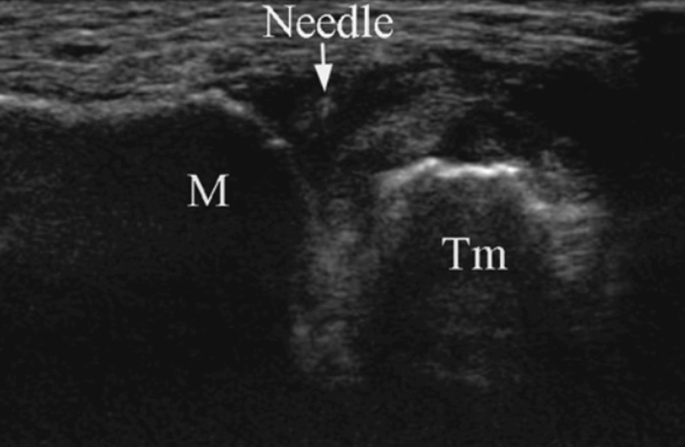

Unlike this picture above I have it done with an ultrasound, which helps guide the needle into the correct space. As the joint space between the bones now are exceedingly small, as arthritis has took over.

Nearly fainted with the left hand, joint seems extra narrow, and though we use depo now which is less liquid, you can still feel the bone space being filled and bones being pushed apart. Right hand the ultrasound shows the joint is gone, it’s jagged and somehow it’s easier to get the needle and liquid in. I waited for a few minutes lying down, to let the fainting feeling and sickness pass. Now home to rest.